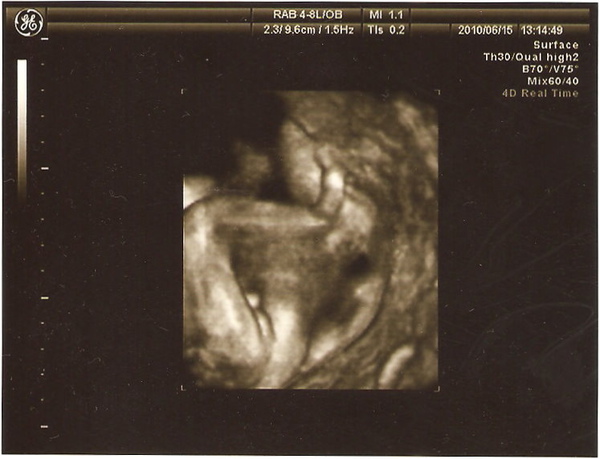

最後這一張..............知道的就知道,可憐的李小果,好沒隱私喔..............

恭喜恭喜~

回覆刪除哈哈,我終於看懂最後一張了!

是男人就會懂~~~